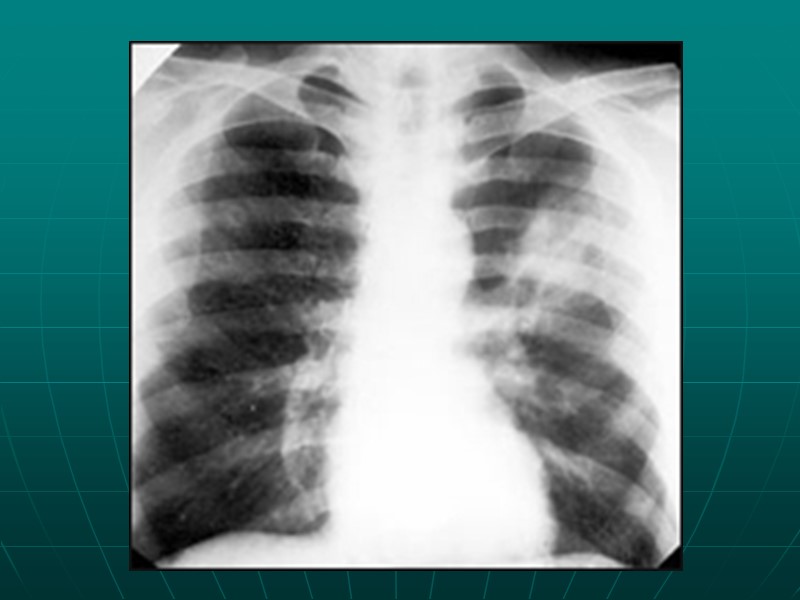

Обязательные исследования при ТЭЛА (проводятся у всех больных) исследование газов артериальной крови, регистрация электрокардиограммы - ЭКГ, рентгенография органов грудной клетки, эхокардиография, перфузионная сцинтиграфия легких/спиральная компьютерная томография, ультразвуковое исследование магистральных вен ног, определение Д-димера);